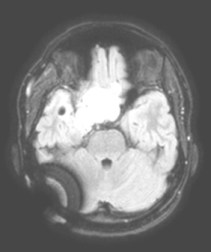

artéfact occasionné apr une valve Sophysa en séquence Flair ; en séquence T2* les images sont totalement illisibles. - les valves réglables contiennent le plus souvent un aimant qui entraîne plus ou moins d’artéfacts radiologiques (cf. ci-contre).